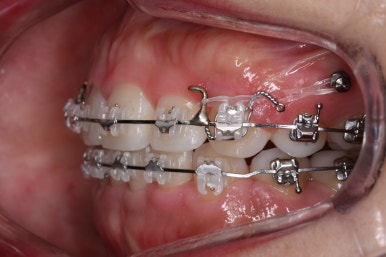

우선 재배열 부터 하였습니다.

브라켓의 위치가 교정을 하는데 있어서 매우 중요하기에 일부분은 먼저 재부착을 하였습니다.

이 후에는 미니스크류를 심어주었어요.

해당 장치를 활용해 윗니를 뒤로 당겨왔습니다.

점점 개선이 되고 있는 모습이 보입니다.

정면으로 맞물렸던 교합도 좋아지고 있으며 이로 인해 자연스레 위아래의 앞뒤 간격도 맞닿게 되고 좁아지고 있습니다.

좌측에서 본 모습도 마찬가지입니다.

발치 후에 남아있던 미세한 공간도 없어졌고 윗니도 후방 이동 되면서 교합이 좋아지고 있습니다.